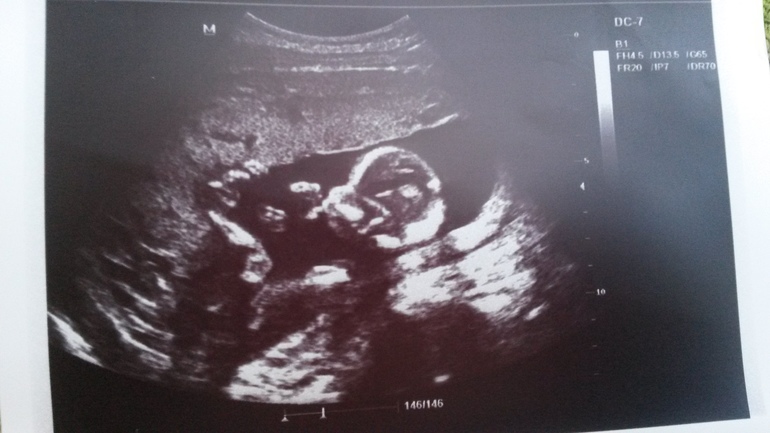

Наша первая фотография)))

Наши будни, наши неделькиСходили мы в пятницу на платное узи. Наша крошка сначала отвернулась от нас спиной и не хотела к нам поворачиваться, зато позволила врачу рассмотреть у себя все органы, плечи и косточки))) Я перед узи схомячила фруктов, чтобы активности прибавить, но хитрая схема не сработала. Кроха лишь руками болтала. Потом она сжалилась над нами и развернулась. Разрешила запечатлеть ее профиль и посмотреть пол! Кроха в это время сосала палец и ножки куда-то вверх замкнуты))) Забавно так - попа, ножки вверху))) признаков мужского пола мы не разглядели. Я вообще ничего между ног там не увидела, но врач сказала, что скорее всего это девочка. Неуверенно как-то. Но на фото, которые тут выкладывают, мальчиков сразу видно. Если конечно у нас там писюн вместе с ногами вверх не уплыл)))

На фото сосем палец, слева ножки у которых вверху видно пальчики и пятку)))

Так мило, такая малышечка, а уже палец сосет))))